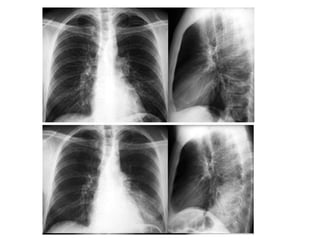

home.comcast.net/~wnor/thoraxradiology.htm

Sistema Respiratório Nariz,boca, faringe, laringe, traquéia e árvore brônquica Dois pulmões

Fornecer oxigênio aosangue e às células Eliminar o dióxido de carbono do sangue Auxiliar na regulação do equilíbrio ácido-básico